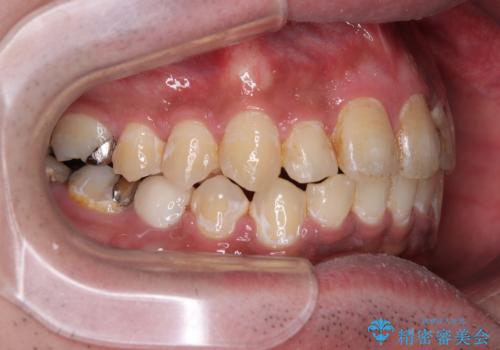

- 主張してる上の前歯を気にして来院された患者様です。

上の前歯が出ているものの、口元が出っ歯というわけではなかったため、非抜歯矯正にて治療を行うこととしました。

下顎に対して上顎歯列が全体的に前方に位置しており、特に右側の奥歯の咬み合わせの前後のズレが大きいため、補助装置を用いて咬み合わせを改善することとしました。

元々むし歯リスクが高かった上に、矯正治療中も磨き残しが多かったため、今後はむし歯治療を行う必要があります。